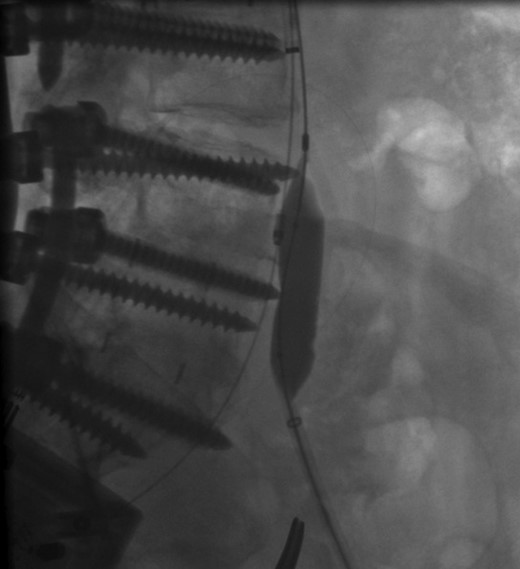

The patient was scheduled for left iliac vein stent placement. During the procedure, impingement was noted upon the posterior aspect of the vein. At this location, there was perforation of a pedicle screw through the anterior cortex of her L5 vertebral body, from prior spinal fusion. This interaction was well visualized during intraluminal inflation of a 12 mm × 40 mm high-pressure balloon (Fig. 2) and was also seen after final stent placement (Fig. 3). Because the screw tip was completely unyielding, a 14 mm × 60 mm Wallstent was used instead of the 16 mm stent we typically use, so as to avoid undue compression of her overlapping right common iliac artery. After the procedure, the patient's symptoms were greatly improved. Follow-up venography performed 4 months postoperatively showed a patent stent with slight eccentric compression at the protruding screw and no evidence of in-stent stenosis.

Perforation of a pedicle screw through the anterior cortex of L5 vertebral body visualized during intraluminal inflation of a 12 mm × 40 mm high-pressure balloon.